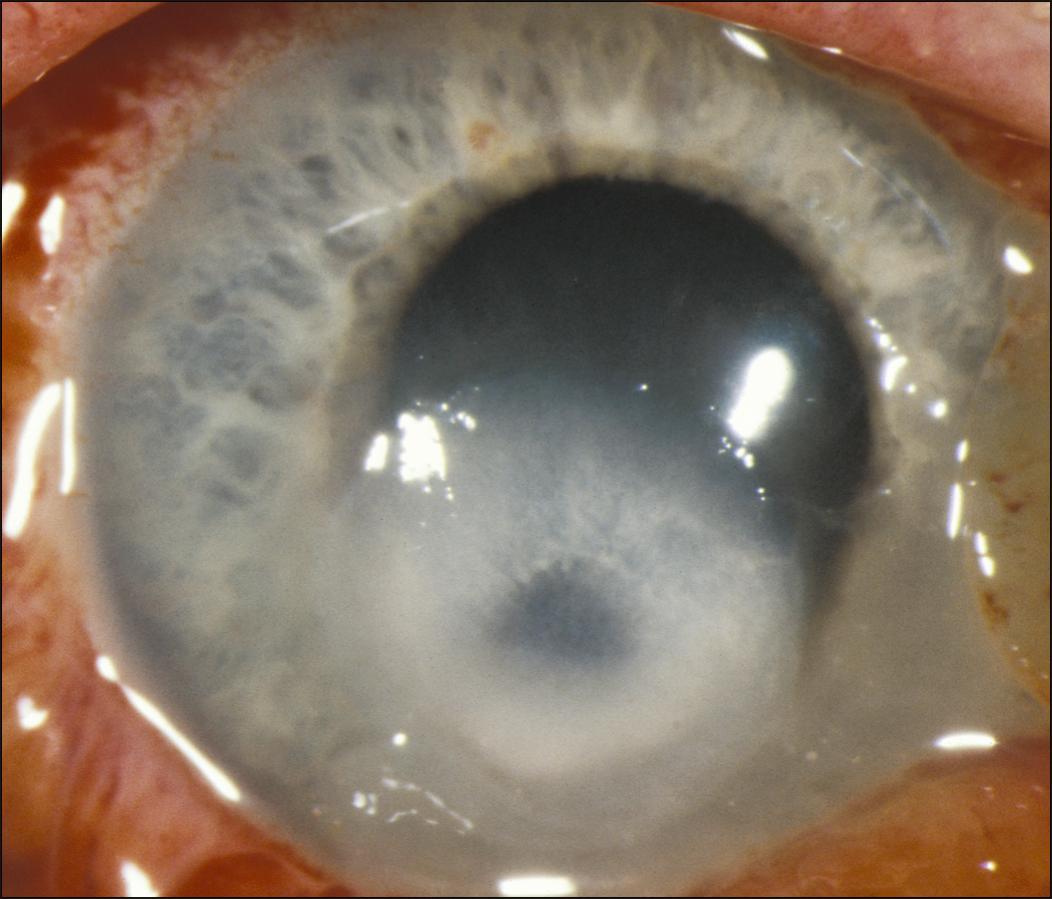

Fig. 99.1, A severe Pseudomonas ulcer developed 1 day after patching an abrasion in a patient who used extended-wear soft lenses. This resulted in severe scarring, and a penetrating keratoplasty was necessary for visual rehabilitation. Patching is contraindicated in contact lens-related abrasions. Treatment should include frequent topical antibiotic ointment or drops with good coverage for Pseudomonas and immediate follow-up for increased pain, decreased vision, or a change in the appearance of the eye.